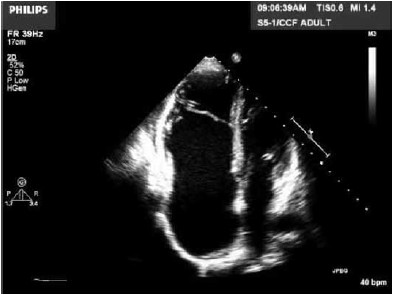

Mulher, 25 anos, apresenta intolerância aos esforços e palpitações. Realiza ecocardiograma apresentado na imagem a seguir.

Assinale a alternativa correta quanto à hipótese diagnóstica.